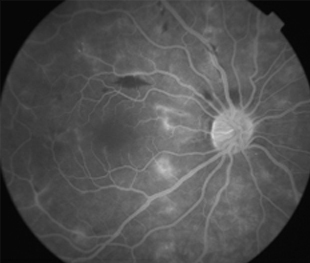

Angiografía OD

- Angiografía: teñido arterial, escape capilar, más tardíamente, no perfusion arteriolar y venular con teñido de las paredes vasculares y dilatación venosa.